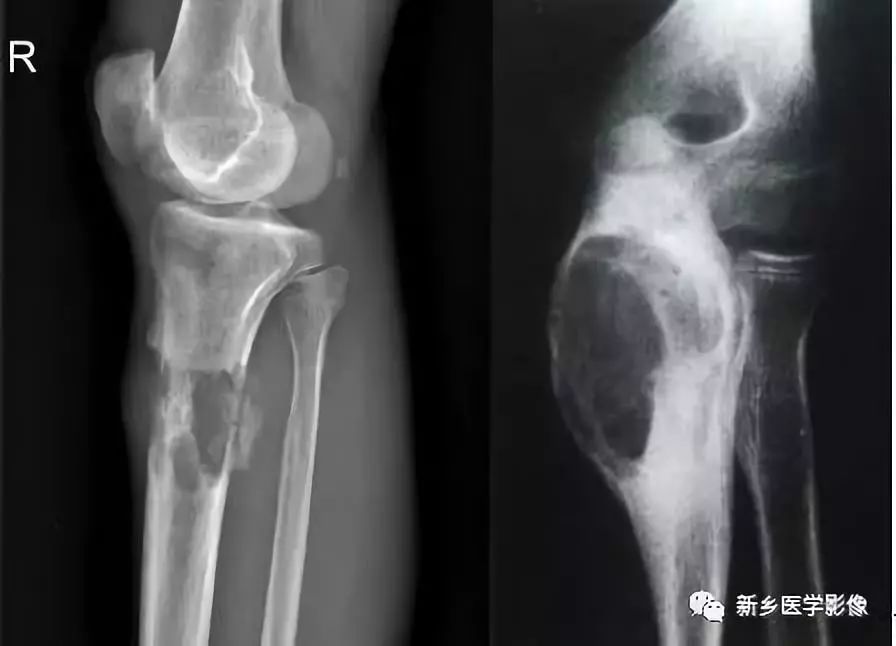

骨质破坏X线图像

a. 膝部X线侧位片示胫骨上段不规则溶骨性破坏,局部见软组织肿块。b.肘关节正位片示尺骨上段膨胀性骨质破坏,边缘骨质硬化,无软组织肿。

骨质破坏见于炎症、肉芽肿、肿瘤或肿瘤样病变。由于病变的性质、发展的快慢和邻近骨质的反应性改变不同,不同病因造成的骨质破坏在X线表现上具有一定的特点。如在炎症的急性期或恶性肿瘤,骨质破坏常较迅速,轮廓多不规则,边界模糊,可称为溶骨性破坏。而炎症的慢性期或良性骨肿瘤,则骨质破坏进展较缓慢,边界清楚,在骨破坏区边缘往往可见一致密的骨质增生硬化带围绕;如造成骨轮廓的膨胀,可称为膨胀性骨破坏。